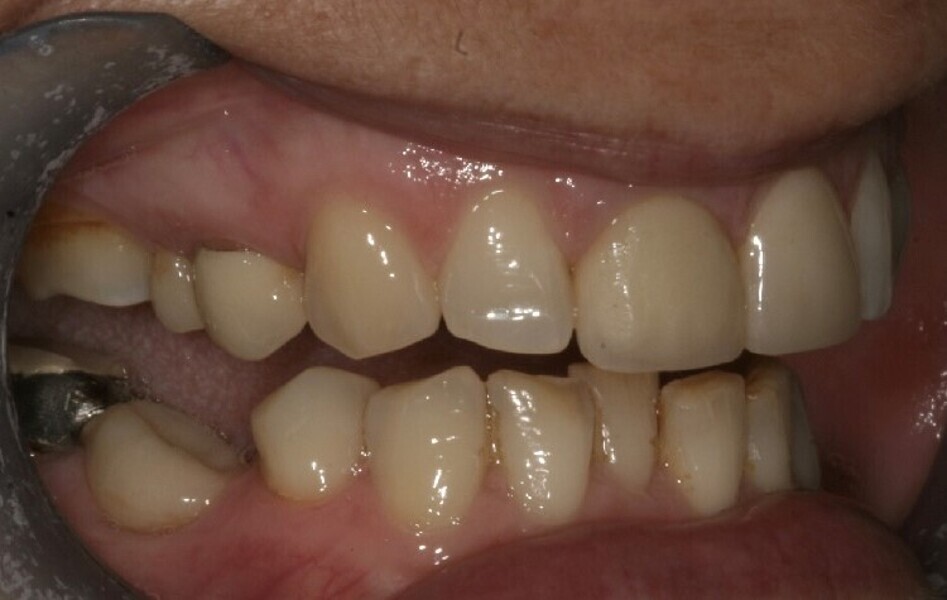

A 48-year-old female patient came to see me in 2004. The patient initially presented because she was unhappy with her two discoloured maxillary central incisors (Fig. 1). She also had chipping and wear of the mandibular teeth and broken posterior bridgework. Her “bite” also felt uncomfortable (Fig. 2).

Fig. 1: 2004—discoloured maxillary central incisors.

Fig. 2: 2004—reduced anterior guidance.

Fig. 3: 2004—wear on the mandibular teeth and crowding.